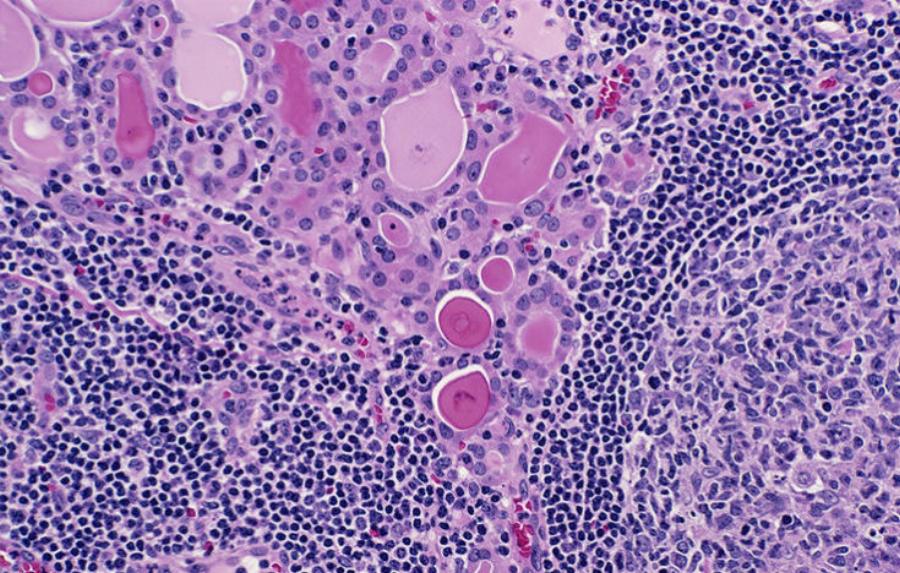

Λύκος

Είναι γυναίκες οι 9 στους 10 πάσχοντες από Συστηματικό Ερυθηματώδη Λύκο. Το αυτοάνοσο που πλήττει τις αρθρώσεις, το δέρμα, τα νεφρά, την καρδιά, τους πνεύμονες, αλλά και πολλά ακόμη σημεία.

Ο λύκος εκδηλώνεται με ένα ευρύ φάσμα συμπτωμάτων, τα οποία μπορεί να εμφανιστούν και σε άλλες παθολογικές καταστάσεις. Έτσι, ο γιατρός πρέπει να αποκλείσει αρχικά άλλες παθολογικές καταστάσεις με βάση το ιστορικό. Την κλινική εξέταση και τις εξετάσεις αίματος. Κάποια συμπτώματα είναι η υπερβολική κούραση, οι πονοκέφαλοι, η διόγκωση και ο πόνος στις αρθρώσεις , ο πυρετός, το πρήξιμο στα χέρια και τα πόδι, ο πόνος στο στήθος, η τριχόπτωση, το εξάνθημα σε σχήμα πεταλούδας στο πρόσωπο (μύτη και μάγουλα).

Η θεραπεία βασίζεται στην λήψη κορτικοστεροειδών και άλλων φαρμάκων που βοηθούν στη μείωση της φλεγμονής. Καταστέλλουν το ανοσοποιητικό και ελαχιστοποιούν τις βλάβες στα διάφορα όργανα.